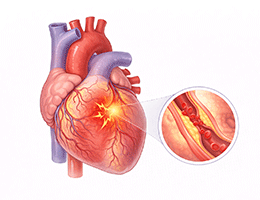

심근경색 (Myocardial Infarction)

협심증 (Angina Pectoris)